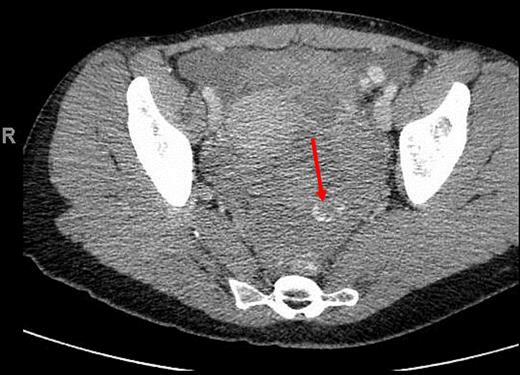

A 34-year-old female with no past medical history was transferred to our emergency department from an outside hospital due to concern for intra-abdominal bleeding. She initially presented with lower abdominal pain immediately following vaginal intercourse described as nonvigorous with the patient mostly ‘on top’, and no history of foreign body use or trauma. CT of the abdomen and pelvis with IV contrast performed at the outside hospital revealed an intra-abdominal hematoma with extravasation of contrast questionably from one of the branches of the left internal iliac artery (Figs 1 and 2). No adnexal lesions were identified on the CT. Upon arrival, the patient was complaining of constant, sharp, severe bilateral lower quadrant abdominal pain, nausea and fatigue. There was no history of loss of consciousness, vomiting, vaginal or rectal bleeding, or hematuria. A past surgical history consisted of appendectomy. Her last menstrual period was 19 days prior to presentation.

CT (axial view) of the pelvis showing extravasation of contrast material into the left pelvis (red arrow).